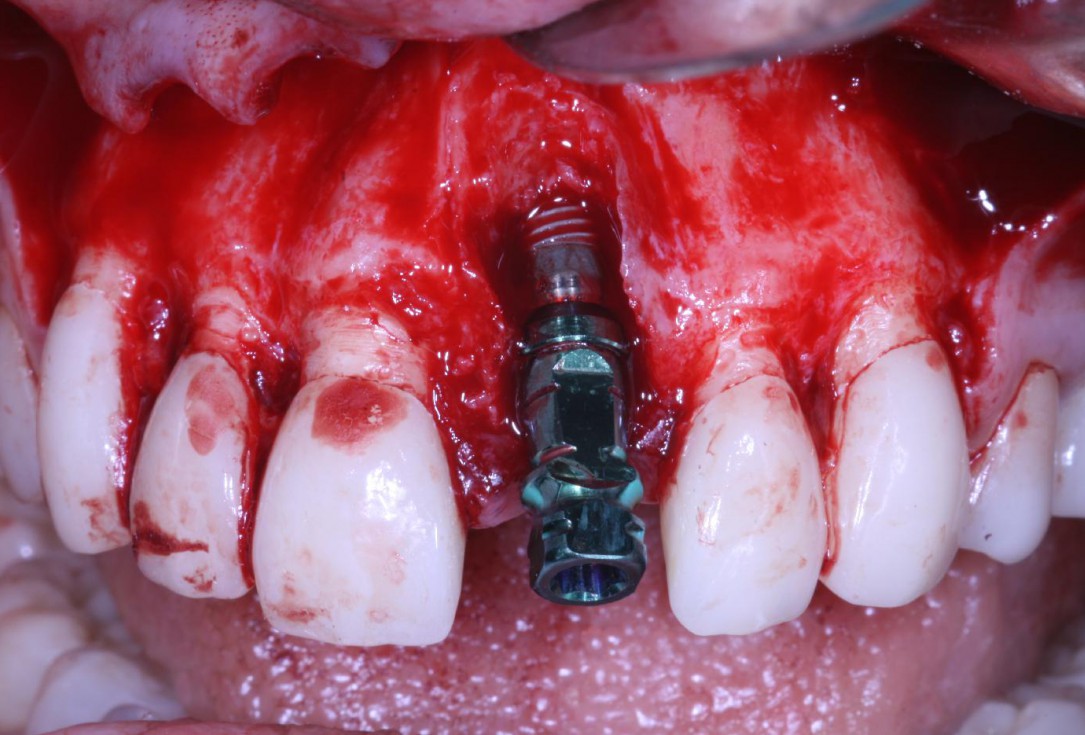

Mucosal thickening around bone level implants - Dr. A. Puisys

Socket seal with mucoderm® punch